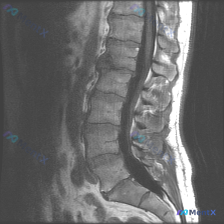

看到一张矢状位腰椎MRI,能直接排除脊柱侧弯吗?

整理到一份影像资料,主诉考虑「脊柱侧弯」,但只放了一张矢状位腰椎MRI T1加权图像。

图像本身的客观表现大概是:

- L1-L5椎体及骶骨轮廓清,高度大致正常,未见明显压缩骨折或滑脱

- 椎体骨髓信号中高,符合脂肪沉积,未见明确骨质破坏

- 椎间盘信号中等,椎间隙未见明显狭窄,硬膜囊前缘较完整

- 脊髓圆锥位置正常,马尾走行自然

- 黄韧带未见明显肥厚,椎旁软组织层次清

单看这张图的描述,好像「没什么大问题」?但结合「脊柱侧弯」的主诉,总觉得哪里不太对。

大家第一眼会怎么考虑?下一步最想补什么检查?